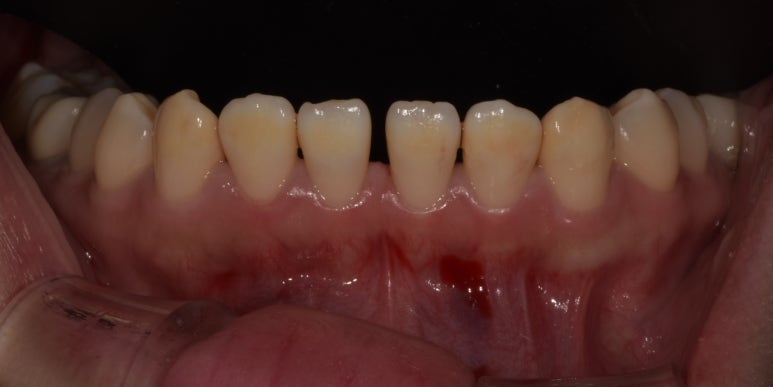

20230411 치료 전

20230422 치료 후